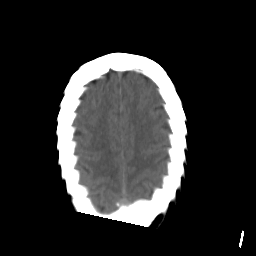

Stroke CT #1 -- Slice #20

[Home][Help][Clinical] Slice 20